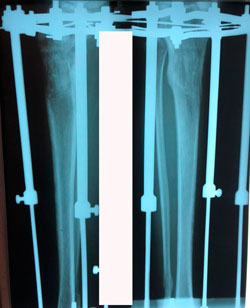

Исходник - 24 года.

Диагноз: врождённое укорочение правой голени на 4 см.

Дата операции - 10.07.2019г.

Костный регенерат в динамике, в процессе удлинения.